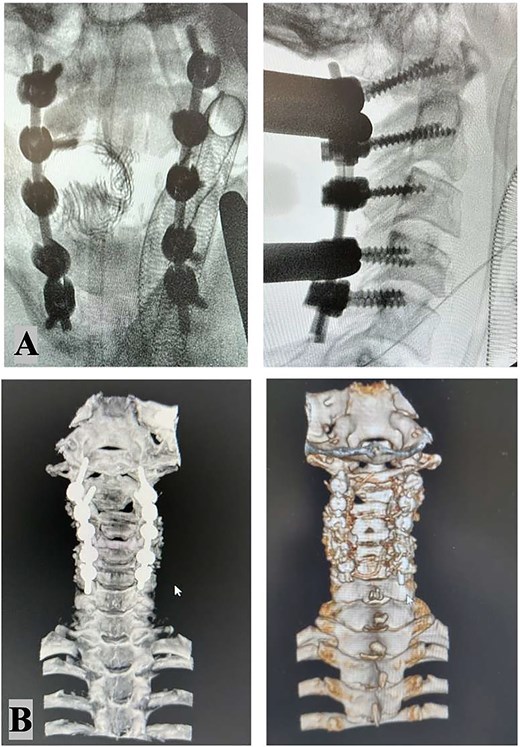

The intricate nature of the injury necessitated thorough evaluation of surgical options, with careful consideration given to systemic, vascular, mechanical, and neurological parameters. The surgical options included external traction, anterior cervical approach, posterior cervical approach, and a combined anterior–posterior approach. Given the presence of bilateral carotid artery dissections, which rendered the vessels exceptionally delicate, an anterior approach was contraindicated due to the heightened risk of iatrogenic vascular injury. Therefore, a posterior-only approach was ultimately selected. The surgical procedure involved unlocking the locked C2–C3 facets on the left side, which required precision drilling and direct manipulation. Realignment was achieved using rod holders as levers, employing counterclockwise rotation of the rods to strategically reposition the lateral masses. To ensure optimal stability with the single posterior approach, fixation was extended to encompass C1, C4, and C5 vertebrae. The patient tolerated the surgical procedure well, and postoperative coronal and 3D CT imaging (Fig. 3) confirmed successful realignment and structural stabilization. Management of the vascular injuries involved starting dual antiplatelet therapy 24 hours after surgery to prevent ischemic or embolic complications, which continued for 6 months. Endovascular treatment of the dissected arteries was performed 15 days following the spinal surgery, addressing the dissection of the right internal carotid artery and the left vertebral artery occlusion.

Intraoperative X-ray: Stable fixation and proper alignment of the cervical spine after C1–2–3–4–5 bilateral screw placement (A). Postoperative CT scan imaging confirmed successful realignment and structural integrity (B).

Postoperative imaging demonstrated stable fixation and proper alignment of the cervical spine. The patient showed improvement in neurological function at discharge, though specific long-term outcomes were not detailed in the available data. Follow-up care focused on monitoring spinal stability and vascular recovery, with no immediate complications reported.